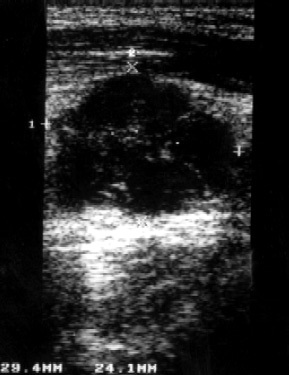

Amikor ultrahang retrosternalis nyirokcsomók keresztül nadklyuchichnvy hozzáférési jogot talált több patológiásán elváltozott nyirokcsomó mérete 5 mm 12,4x14,3 és 22,3x15,4 mm (3. ábra). Más csoportok nyirokcsomók felületét helyen (hónaljban és kulcscsont alatti) nem válnak láthatóvá, ami arra utal, hogy a hiánya rosszindulatú. A folyamat során az ultrahang egy beszélgetés során a beteg kiderül, hogy közben a 3 hónapos zavar zsémbes fájdalom az ágyéki, ott is egyfajta diszkomfort, fekvő testhelyzetben. Amikor ultrahang retroperitoneumban 3-5 ágyékcsigolyák konglomerátum észleltünk kórosan módosított aorta nyirokcsomókban 37,9x41,8 mm (ábra. 4). Leírunk a hashártya mögötti nyirokcsomókból értékesítik kapu terület a bal vese helyét, hogy zavart a vizelet kiáramlását (ábra. 5). Echografically kiderült, egy bal oldali hydronephrosist (ábra. 6.).